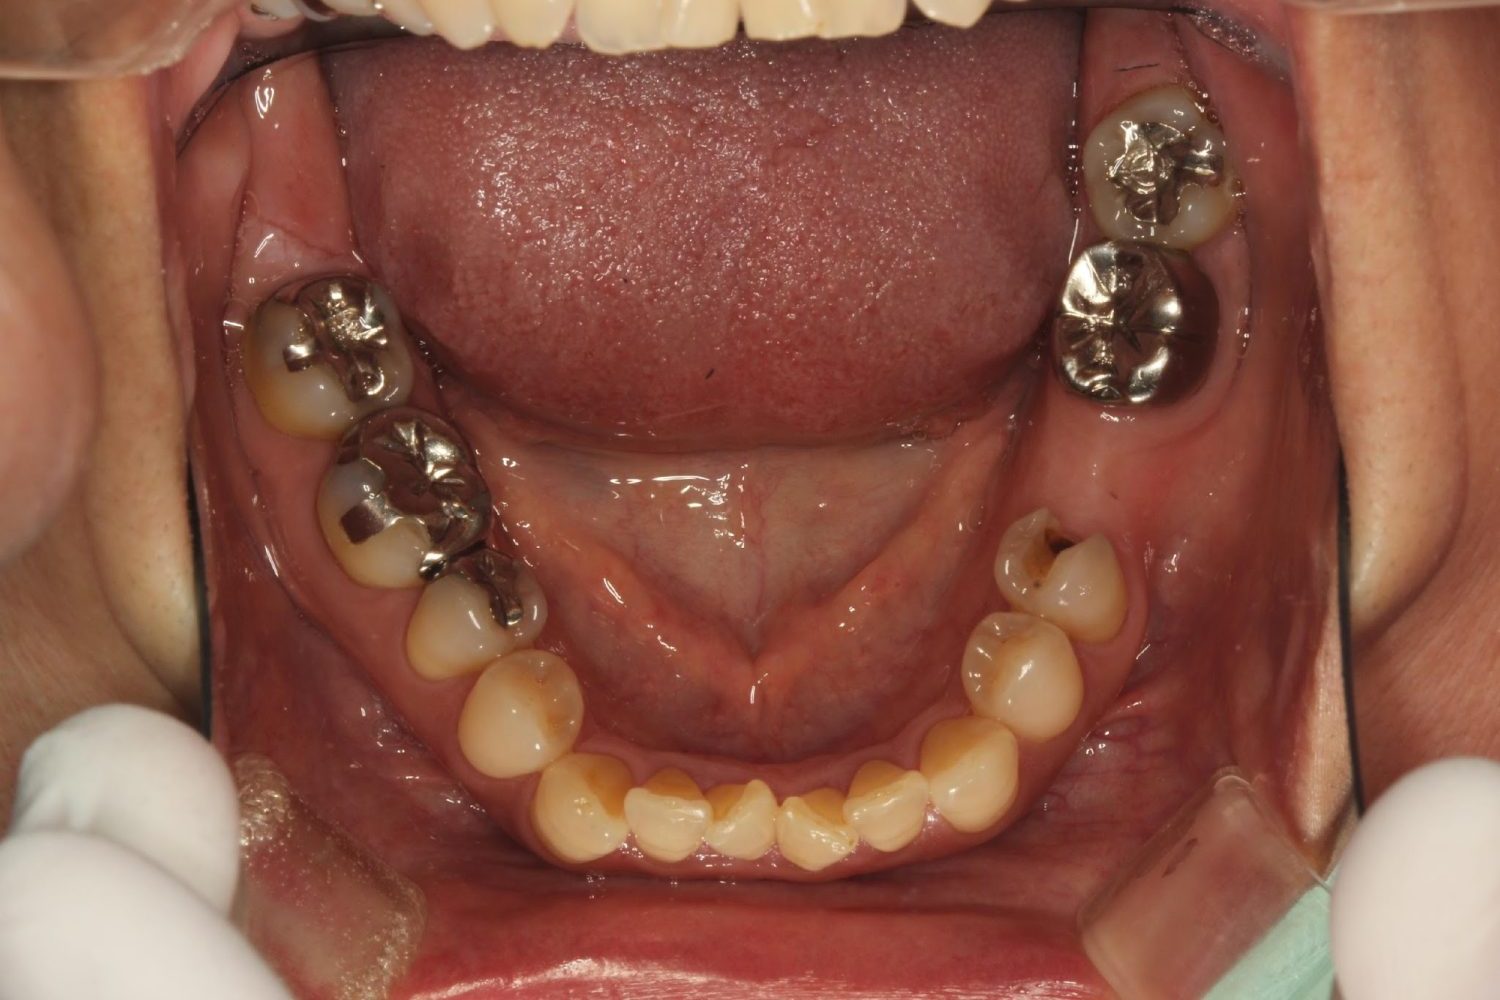

インプラント治療の症例紹介⑥

Before

After

主訴

咬めるようになりたい

治療内容

保存不可能な歯の抜歯、上下の咬み合わせを揃えて欠損部にインプラント治療

治療費

2,508,000円(税込)

治療期間

19ヶ月

通院回数

26回

想定されたリスク

※血糖値の高い方で、咬めるようになると高血糖となる可能性があるため食事制限が必要となる。インプラント周囲炎の恐れがありました。

歯の欠損による対合歯の挺出等を修正し咬合平面を揃えた症例